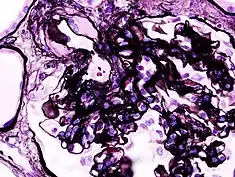

| Microscopic image of diabetic glomerulosclerosis, the main cause of nephrotic syndrome in adults. | |

_PAM.jpg.webp)

Secondary causes of nephrotic syndrome have the same histologic patterns as the primary causes, though they may exhibit some difference suggesting a secondary cause, such as inclusion bodies.[22] They are usually described by the underlying cause.